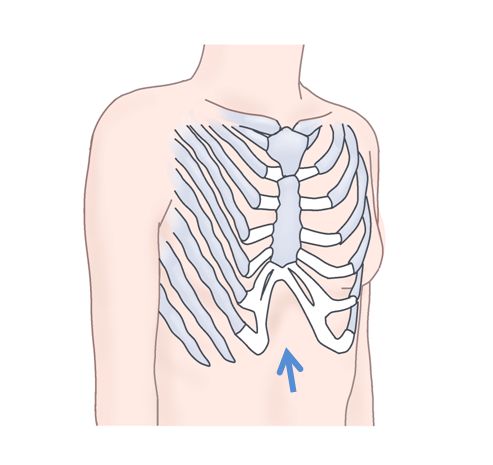

上のイラストは右の胸がへこんでいる状態を示しています。

肋骨と胸骨が曲がったり、歪んだりしているんですね。

これは肋軟骨の発育が過剰だったり、

姿勢が影響したりすることで起こります。

内部に心臓があるため、左の胸がやや右よりも高い前に出ているということも

多いようです。